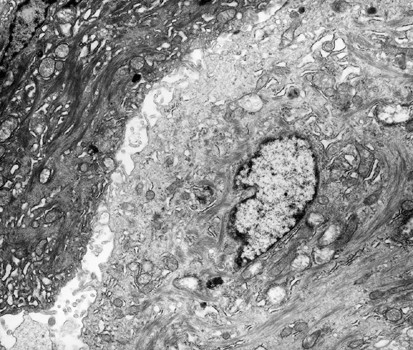

Figure 8 | Modern Pathology